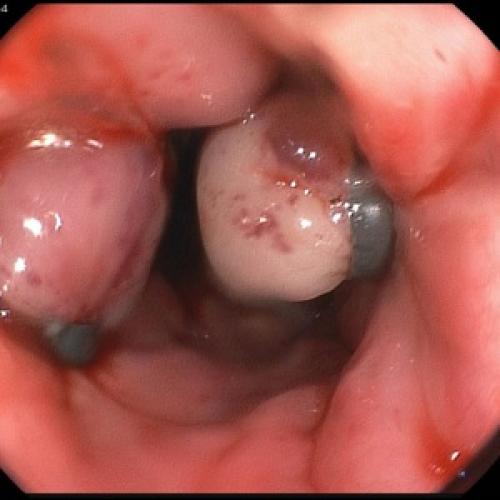

Пациентам с предположительным клиническим диагнозом острого панкреатита показано выполнение ЭГДС (дифференциальный диагноз с язвенным поражением гастродуоденальной зоны, осмотр БДС).